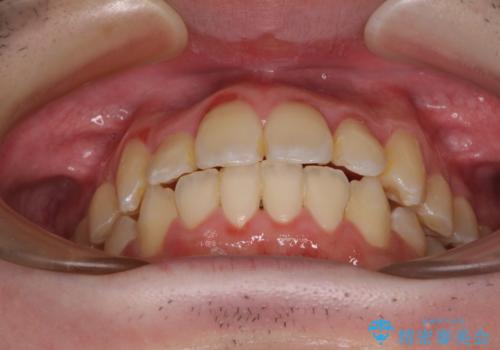

全顎的なクロスバイト 補助装置を用いてワイヤー矯正

- 八重歯や奥歯の噛みにくさを気にして来院された患者様です。

前歯のクロスバイトや八重歯の他に、左右最後臼歯のシザーズバイト(鋏状咬合)が認められました。

シザーズバイト改善のために補助装置を使用しながら、ワイヤー装置にて全体の歯列を整えることとしました。